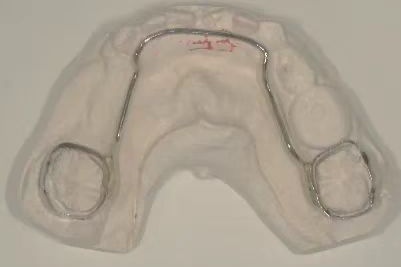

舌弓式间隙保持器

Nance弓(腭弓)式间隙保持器,主要适用于单侧或双侧多颗乳牙早失的治疗。